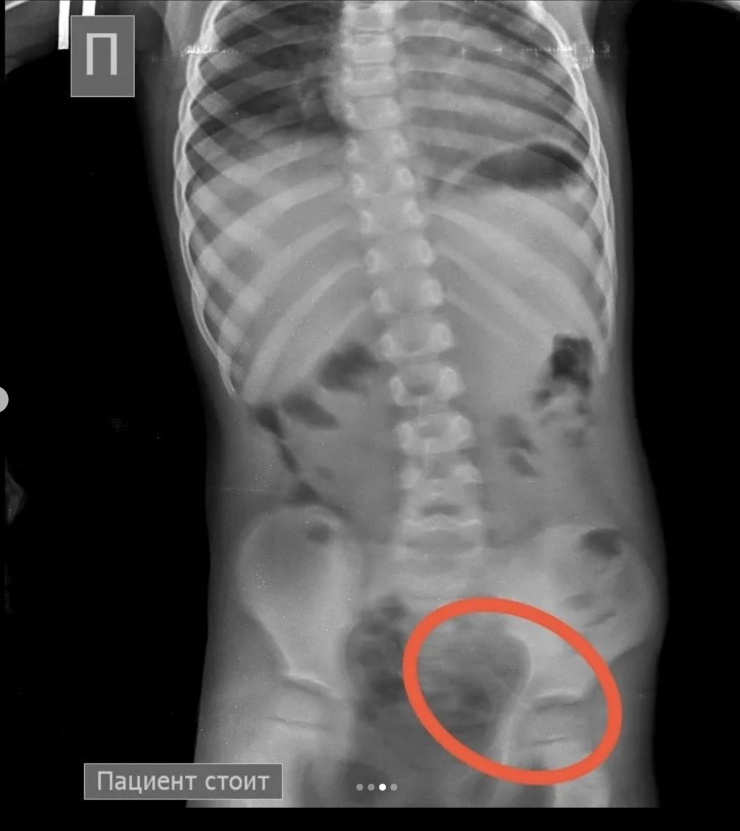

Однако после этого в ходе наблюдения ребенка на контрольной R–грамме брюшной полости обнаружена еще и четвертая игла в проекции таза.

"Проведена колоноскопия, и из сигмовидной кишки удалена последняя игла, которая концом была зафиксирована в слизистую кишечника. В настоящее время ребенок в удовлетворительном состоянии выписан домой", - сообщили врачи.